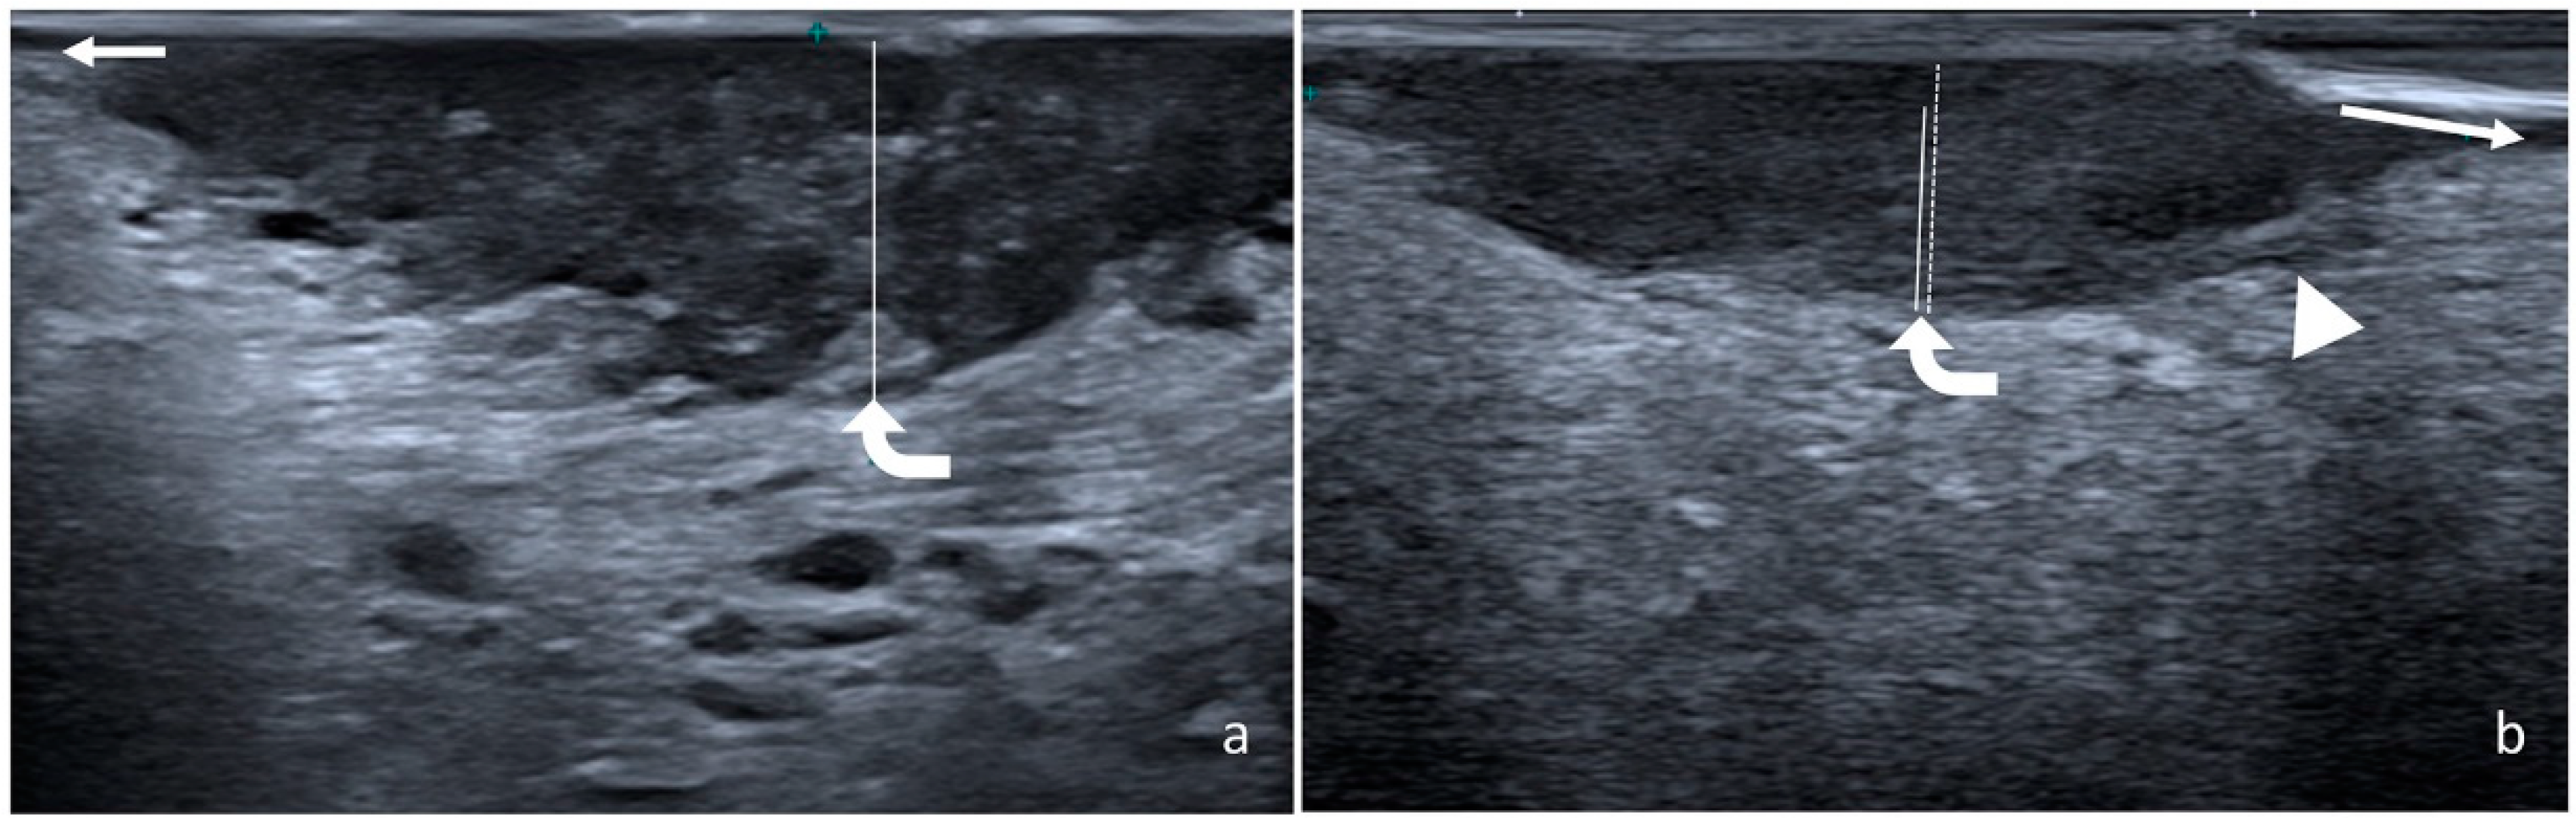

2.2. Measurement of Radiological and Pathological DOI

- Iida, Y.; Kamijo, T.; Kusafuka, K.; Omae, K.; Nishiya, Y.; Hamaguchi, N.; Morita, K.; Onitsuka, T. Depth of Invasion in Superficial Oral Tongue Carcinoma Quantified Using Intraoral Ultrasonography. Laryngoscope 2018, 128, 2778–2782. [Google Scholar] [CrossRef]

- Filauro, M.; Missale, F.; Marchi, F.; Iandelli, A.; Carobbio, A.L.C.; Mazzola, F.; Parrinello, G.; Barabino, E.; Cittadini, G.; Farina, D.; et al. Intraoral Ultrasonography in the Assessment of DOI in Oral Cavity Squamous Cell Carcinoma: A Comparison with Magnetic Resonance and Histopathology. Eur. Arch. Oto Rhino Laryngol. 2021, 278, 2943–2952. [Google Scholar] [CrossRef]

- Rocchetti, F.; Tenore, G.; Montori, A.; Cassoni, A.; Cantisani, V.; di Segni, M.; di Gioia, C.R.T.; Carletti, R.; Valentini, V.; Polimeni, A.; et al. Preoperative Evaluation of Tumor Depth of Invasion in Oral Squamous Cell Carcinoma with Intraoral Ultrasonography: A Retrospective Study. Oral Surg. Oral Med. Oral Pathol. Oral Radiol. 2021, 131, 130–138. [Google Scholar] [CrossRef]

- Takamura, M.; Kobayashi, T.; Nikkuni, Y.; Katsura, K.; Yamazaki, M.; Maruyama, S.; Tanuma, J.; Hayashi, T. A Comparative Study between CT, MRI, and Intraoral US for the Evaluation of the Depth of Invasion in Early Stage (T1/T2) Tongue Squamous Cell Carcinoma. Oral Radiol. 2022, 38, 114–125. [Google Scholar] [CrossRef]

- Noorlag, R.; Klein Nulent, T.J.W.; Delwel, V.E.J.; Pameijer, F.A.; Willems, S.M.; de Bree, R.; van Es, R.J.J. Assessment of Tumour Depth in Early Tongue Cancer: Accuracy of MRI and Intraoral Ultrasound. Oral Oncol. 2020, 110, 104895. [Google Scholar] [CrossRef]